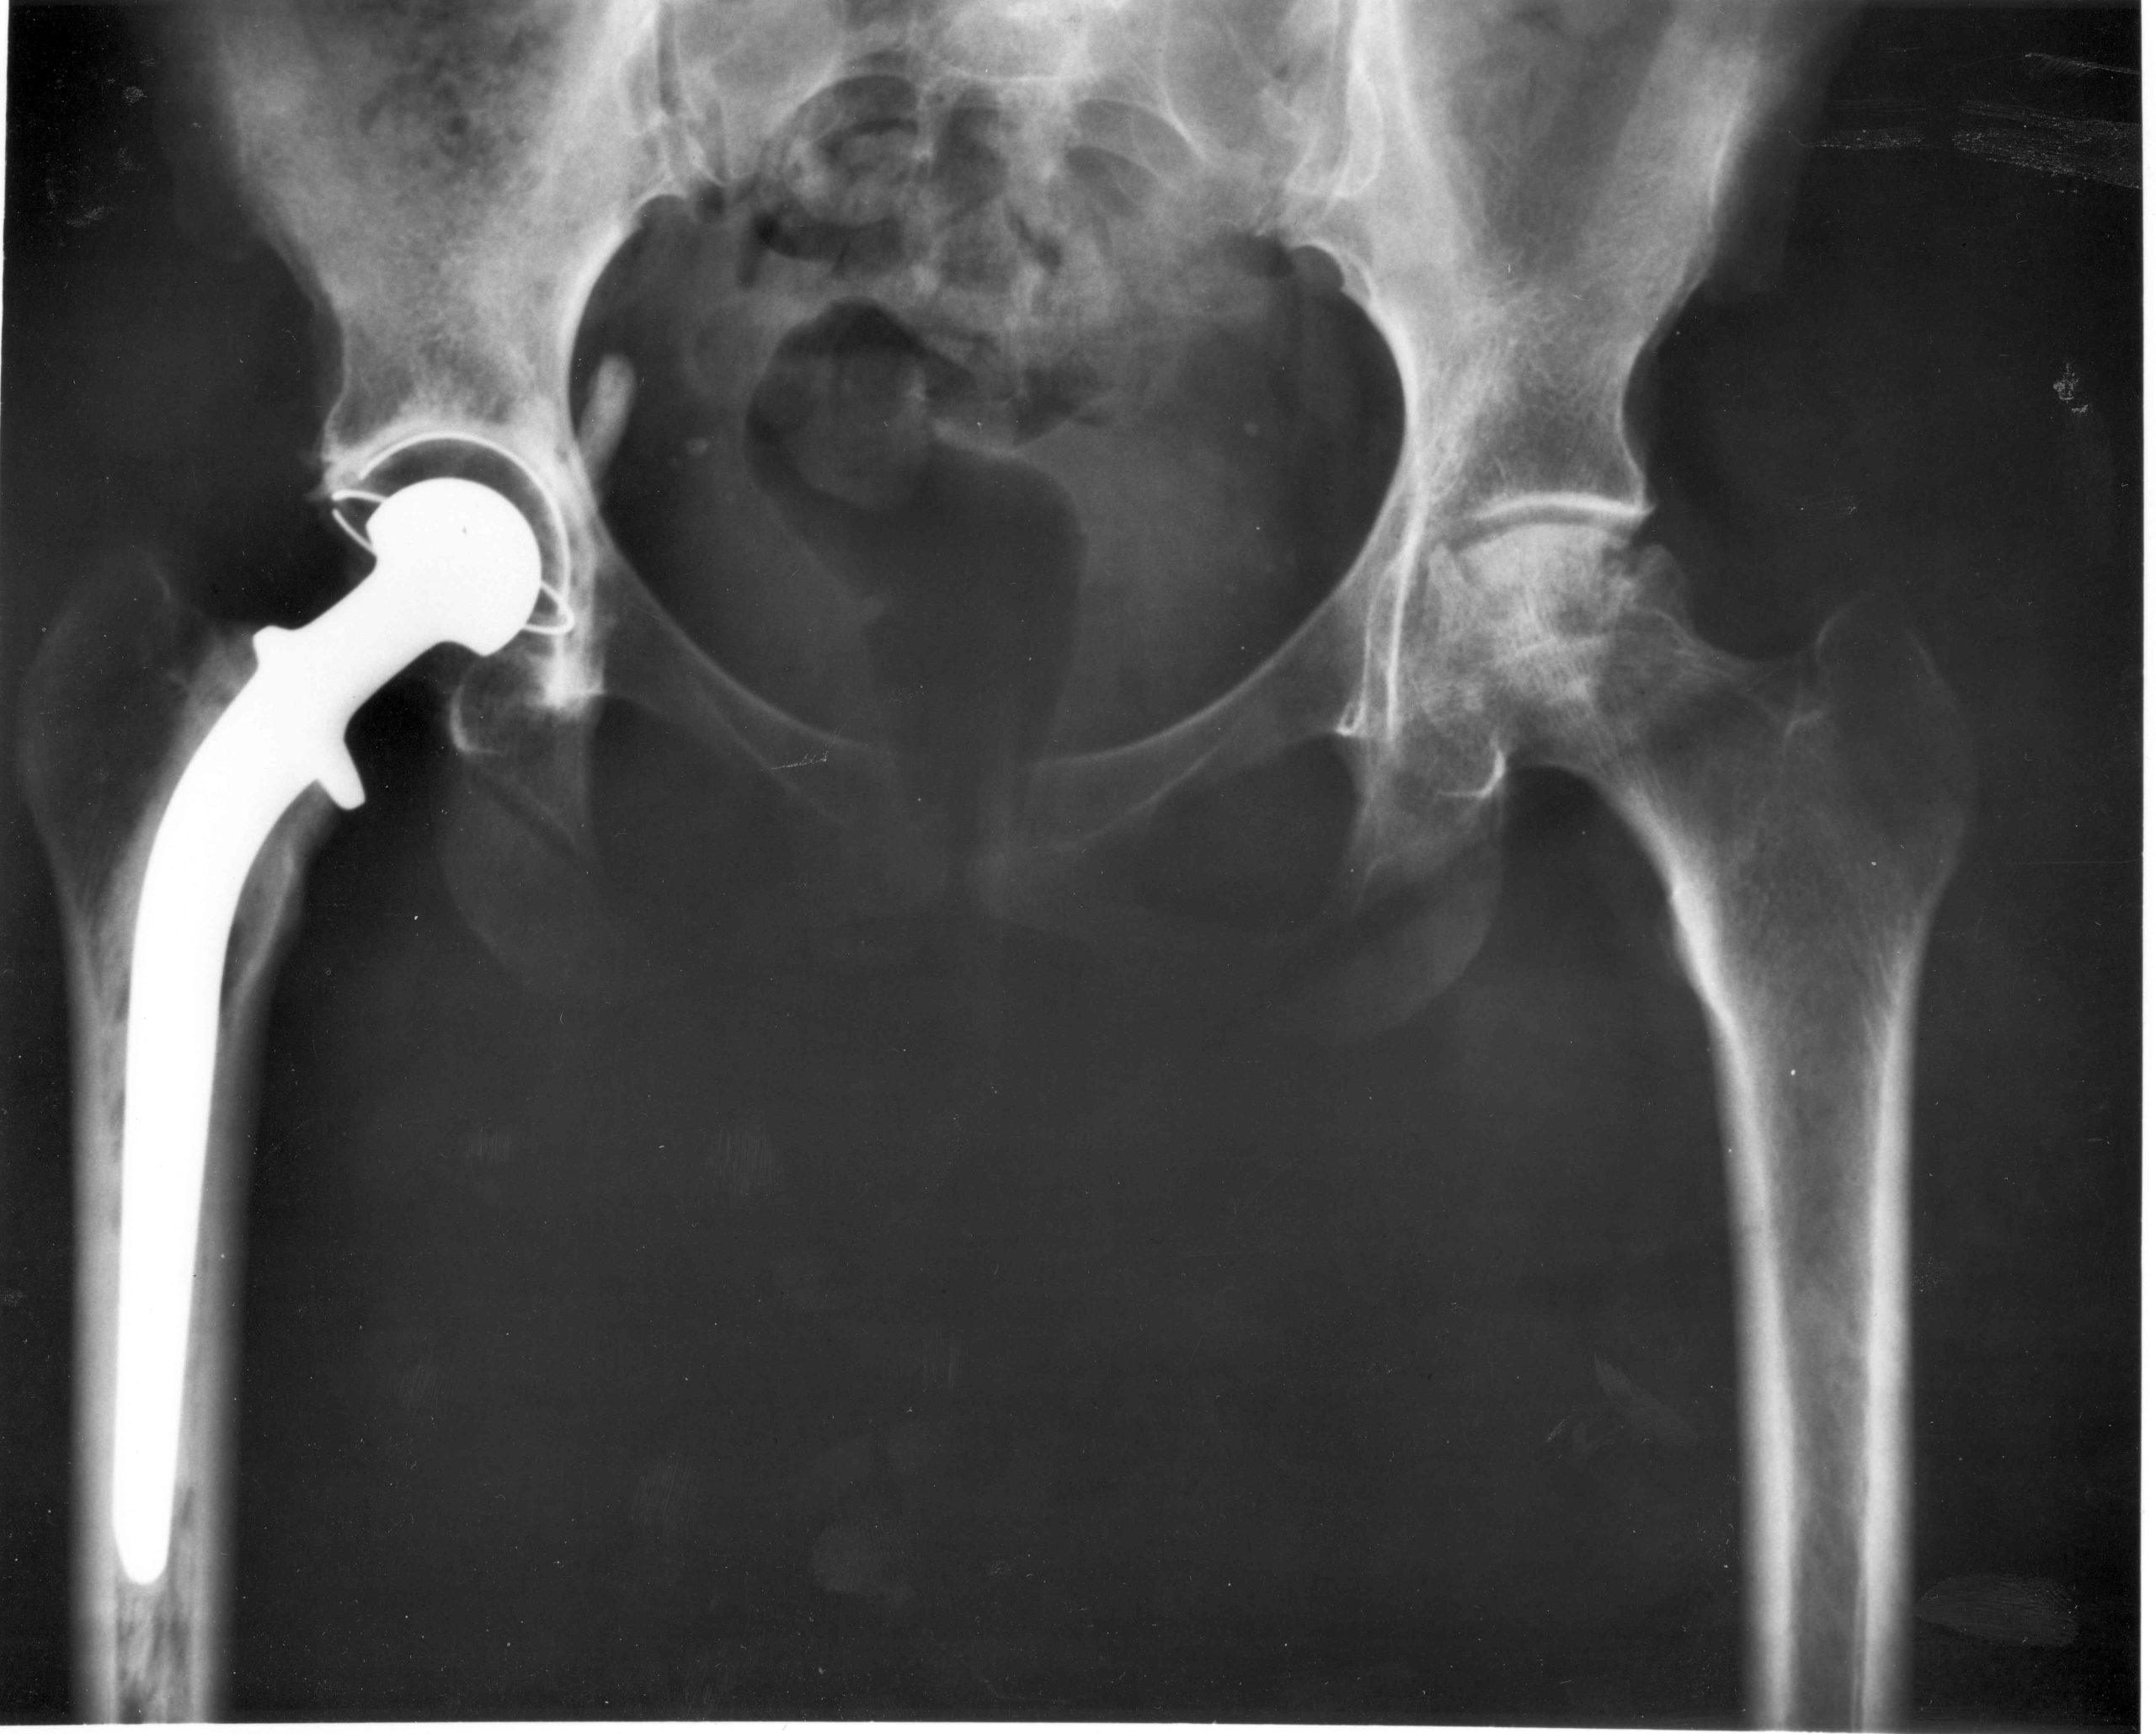

Dobór modalności jest decyzją inżynieryjno-kliniczną. Jeśli pytanie dotyczy architektury kostnej i mineralizacji, przewagę oferują techniki rentgenowskie i CT. Kiedy liczy się kontrast tkanek miękkich, spektroskopia i funkcjonalność — MRI wraz z wariantami fMRI i obrazowaniem przemieszczeń chemicznych. W ocenie perfuzji i metabolizmu korzysta się z radiofarmaceutyków i detekcji gamma (SPECT, PET). Ultradźwięki, dzięki transduktorom piezoelektrycznym, pozwalają łączyć obrazowanie morfologiczne z pomiarem hemodynamiki (Doppler). Integracja danych bywa realizowana od strony sprzętowej (hybrydy PET/CT) lub programowej (rejestracja obrazów, fuzja i mapowanie parametryczne). Podręcznik porządkuje te techniki w sposób modułowy, podkreślając, że warstwa rekonstrukcyjna i obróbka obrazu są równie istotne, co sama aparatura.

Sekcja instrumentów i urządzeń medycznych spina nacisk na jakość sygnału z realnymi konstrukcjami klinicznymi. Wzmacniacze biopotencjałów, układy pomiaru ciśnienia i przepływu, defibrylatory zewnętrzne i wszczepialne, stymulatory, urządzenia anestezjologiczne, respiratory czy pompy infuzyjne — wszystkie te klasy wyrobów przenoszą wymagania z warstwy sensoringu i analizy na warstwę systemową: zasilanie, bezpieczeństwo, izolację, algorytmy sterowania i interfejs człowiek–maszyna. Historyczny skok od narzędzi ręcznych do złożonych systemów wielomodalnych był możliwy dzięki integracji elektroniki, materiałoznawstwa, informatyki oraz zarządzania ryzykiem.

Chociaż główny nacisk kładziemy na czujniki i sygnały, inżynieria biomedyczna łączy się nierozerwalnie z materiałoznawstwem i planowaniem zabiegów stomatologicznych. Implantologia dentystyczna stanowi przykład, gdzie obrazowanie (CBCT/CT, MRI w specyficznych aplikacjach, US wewnątrzustny), czujniki (pomiar stabilności implantów, sił okluzyjnych), analiza sygnałów (monitoring gojenia) i materiały (stopy tytanu, bioceramika) muszą być traktowane jako system. Decyzje o charakterystyce powierzchni implantu, stanie kości, jakości łoża i sposobie obciążenia protetycznego wynikają z danych, których wiarygodność buduje się od pierwszego styku sensora z pacjentem po końcową walidację kliniczną. Ramy materiałowe i czujnikowe w ujęciu kompendium wspierają ten tok: sekcje biomateriałów twardych i miękkich są logicznie sprzężone z sekcjami sensoringu i obrazowania, co podkreśla interdyscyplinarny charakter projektowania terapii.